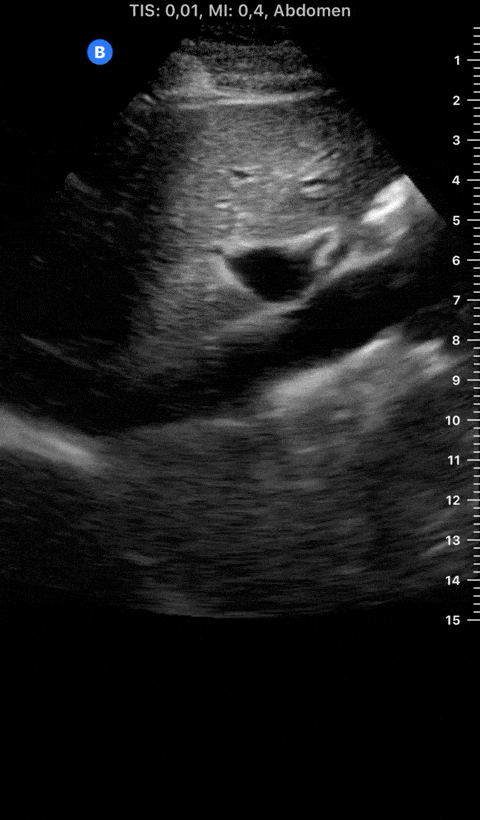

The IVC diameter changes depending on intravascular volume status, and normally, the IVC collapses during spontaneous inspiration. Therefore, the IVC diameter represents a non-invasive method for estimating central venous pressure (CVP). The evidence suggests that in spontaneously breathing patients, there is a good correlation between the sonographic estimation of CVP and values measured with invasive methods (2). IVC filling and CVP, however, allow only a rough correlation with volume status, and the sonographic estimation of preload should at least include the assessment of the LV and the Lung. Thus, it is better to think of IVC filling as an indicator of fluid tolerance, instead of a determinant of fluid responsiveness (6).

IVC exploration is best from the subxiphoid approach with longitudinal and transverse images. The IVC should be assessed in terms of overall size and collapsibility. The diameter is typically measured at its largest (end of expiration) at 1-2 cm distal to where the hepatic veins join the vena cava. An IVC diameter of ≥ 2 cm, especially with minimal or no collapsibility, is considered plethoric and correlates with increased RA pressure. An IVC of < 1 cm, particularly with complete collapse, is considered flat and indicates low preload and potential fluid responsiveness. An IVC diameter between 1 and 2 cm is typically normal.

PITFALLS

In a long-axis view, beware of not sliding off the centre of the vessel, as this will underestimate the size of the IVC and overestimate its collapse. Obtaining long and short axis views may help avoid this pitfall. Another mistake is confusing the descending aorta for the IVC, particularly when scanning in long-axis. Although the IVC may appear to pulsate, the aorta has a thicker wall, and its position is to the patient’s left. Following the IVC upwards will reveal the hepatic veins junction and the entrance to the RA, while the aorta will travel behind the heart. The IVC moves both anterolaterally and craniocaudally with inspiration, and this should be considered during visualization or measuring. For this very reason, measuring in M-mode is not recommended as it would not be accurate.

SHOCK

In a shocked patient, a flat or highly collapsible IVC correlates well with low preload estates (hypovolaemia, haemorrhage, sepsis). Yet by itself, a small IVC is not enough to define low preload and could also represent a normal finding.

Conversely, a distended, not collapsing IVC suggests distal obstruction in a shocked patient. Potential causes include LV failure, massive PE, tension pneumothorax and cardiac tamponade. Nonetheless, there are other causes of elevated cava / RA pressure, such as chronic pulmonary hypertension.